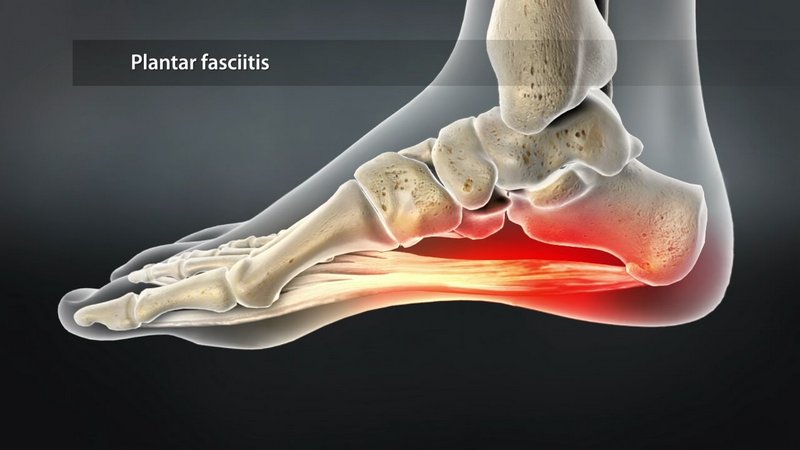

Η πελματιαία απονεύρωση (plantar fasciitis) είναι ουσιαστικά μια δεσμίδα ινών κάτω από το δέρμα του πέλματος, η οποία συνδέει τα μετατάρσια με την πτέρνα, έχει αρκετή ελαστικότητα και παίζει σημαντικό ρόλο σε όλες τις λειτουργίες του ποδιού, όπως στην όρθια στάση, τη βάδιση και το τρέξιμο, ενώ ταυτόχρονα υποστηρίζει την καμάρα.

Αρχικά ο ασθενής νιώθει ερεθισμένη την περιοχή του πέλματος και ο πόνος είναι αρκετά έντονος κατά την ορθοστασία και ακόμα περισσότερο κατά τη βάδιση ή το τρέξιμο. Μάλιστα, ο πόνος είναι πολύ πιο έντονος μετά από ένα διάστημα ανάπαυσης, με προοδευτική μείωση σε κάθε βήμα.

Πολλές φορές στην ακτινογραφία εντοπίζεται και η ύπαρξη άκανθας πτέρνας, η οποία είναι ένα οστεόφυτο - μια οστέινη ουσιαστικά ανάπτυξη ή προέκταση του οστού της πτέρνας στο κάτω μέρος του - το οποίο ο ασθενής μπορεί να το νιώθει κάποιες φορές σαν “καρφί” που πιέζει τα νεύρα στην περιοχή προκαλώντας πόνο. Η άκανθα πτέρνας λανθασμένα συνδεόταν για χρόνια με την πελματιαία απονευρωσίτιδα, αφού μόνο το 5% όσων έχουν άκανθα εμφανίζουν συμπτώματα πελματιαίας απονευρωσίτιδας. Η άκανθα πτέρνας δεν είναι το αίτιο της απονευρωσίτιδας αλλά το αποτέλεσμα χρόνιων τραυματισμών της πελματιαίας απονεύρωσης.